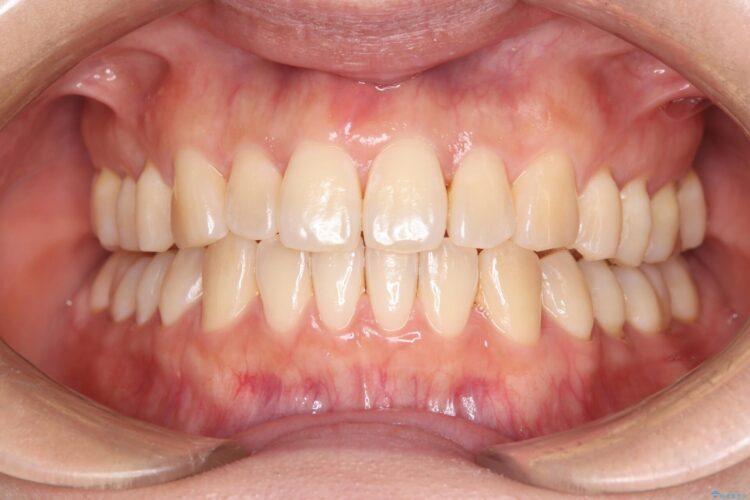

治療後について

かみ合わせを整えるためにゴム掛けも併用して治療を行いました。

患者様にマウスピースの使用とゴム掛けを頑張っていただいたおかげでリファイメント(マウスピースの再発注)も1回で終了することができました。